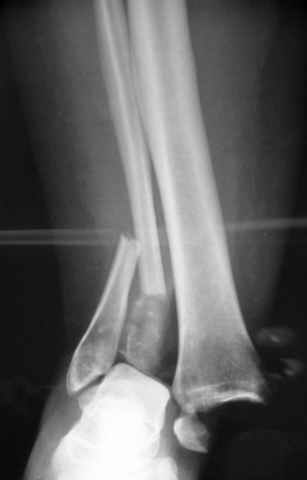

Pilon fracture:

-Появляется ориентир и остов, на чем можно строить восстановление, почему сперва малоберцовую, впервые обьяснили и описали (Pylon type and Ankle fractures) в середине 50х Rienau и Gay.

Восстановливая длину и ротацию малоберцовой кости, затем относительно легче произвести реставрацию остальных элементов перелома дистального эпиметафиза болшеберцовой кости.

где исследования на трупах показали, что малоберцовая кость участвует в стабильности голеностопного сустава, поддерживая наклон тарана (talar tilt) за счет связок. После ознакомления работой Ramsey в ортопедию ввели термин "при переломах голеностопного сустава смещенная

таранная кость следует за малоберцовой костью" т.е. связка не рвется, а тянет таран за собой, поэтому восстановление малоберцовой кости в

первую очередь, затем остальных элементов - стал классическим при лечении данной патолгии. Латеральная колонна (столб), дистальный

конец малоберцевой кости, к нему прикрепляется латеральный суставной фрагмент дистального эпиметафиза большеберцовой кости (как на снимке)

и таранная кость, которые при репозиции малоберцовой кости репонируются автоматически.

Из работ Ramsey and Hamilton, Yablon et., укорочения на 1мм

малоберцовой кости, уменьшает на 42% контактную поверхность между

малоберцевой и таранной кости, которое в свою очередь приводит к

увеличению давления на остальные части суставной поверхности, что

является предпосылкой раннего артроза.